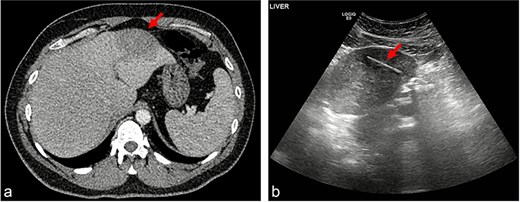

A gentleman in his 30s, previously healthy, presented to the emergency department of a district general hospital with nausea, upper abdominal pain, and fever. He had upper abdominal tenderness but no guarding, leucocytosis, and raised inflammatory markers. A computed tomography (CT) scan revealed a 6-cm hypoattenuating lesion in the left liver lobe (Fig. 1a). All other observations were normal, and he was admitted for intravenous antibiotics. Magnetic resonance imaging demonstrated a hepatic abscess. His symptoms and fever resolved with conservative management, and he was discharged.

(a) Hypoattenuating lesion in the left lobe of the liver; (b) linear hypoechoic structure within a hypoechoic lesion.

A follow-up outpatient ultrasound (US) scan to assess abscess resolution revealed a 4-cm linear hypoechoic structure within the liver (Fig. 1b), raising the suspicion of a FB. This finding was subsequently linked to the patient presenting to the emergency department with abdominal pain after accidentally ingesting the tip of a cocktail stick, which had broken off while eating, a few weeks before his inpatient admission. At the time, he had been well with normal bloods, a soft non-tender abdomen and normal plain radiography, and discharged with the expectation that the stick will pass through without complications.